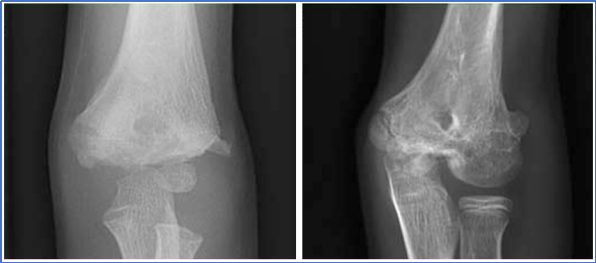

儿童肱骨外髁骨折是儿童肘关节第二常见骨折,仅次于肱骨髁上骨折,占儿童上肢骨折的12%-20%。高发于4-10岁;因软骨成分比例高,X线片仅显示骨化部分,实际骨折块可能更大,易造成漏诊或误诊。属于Salter-Harris II或IV型骨骺损伤。

X线评估必须包含三个位置:肘关节正位、侧位和内斜位,缺一不可。内斜位能最大程度显示骨折线位置和移位,揭示其他体位遗漏的细节。

图6:A 左肘正位X线片,轻度移位,内外侧间隙宽度相同。B 同一肘部的内斜位X线片显示移位较大。

图7: 侧位片需关注Thurstan Holland征(后侧三角形骨片),这是诊断的有力证据。

图8: X线上骨折移位情况不清晰;但CT检查能精准判断骨折块移位情况;

图9A 右肘关节前后位(正位)X 线片:显示外侧皮质 3 期骨折,外侧间隙极小,移位≤2 mm。B 内斜位 X 线片:显示骨折线贯穿肱骨外髁,延伸入关节内,骨折间隙外侧与内侧宽度一致。C 短 T1 加权反转恢复(STIR)磁共振成像:显示软骨完全断裂。